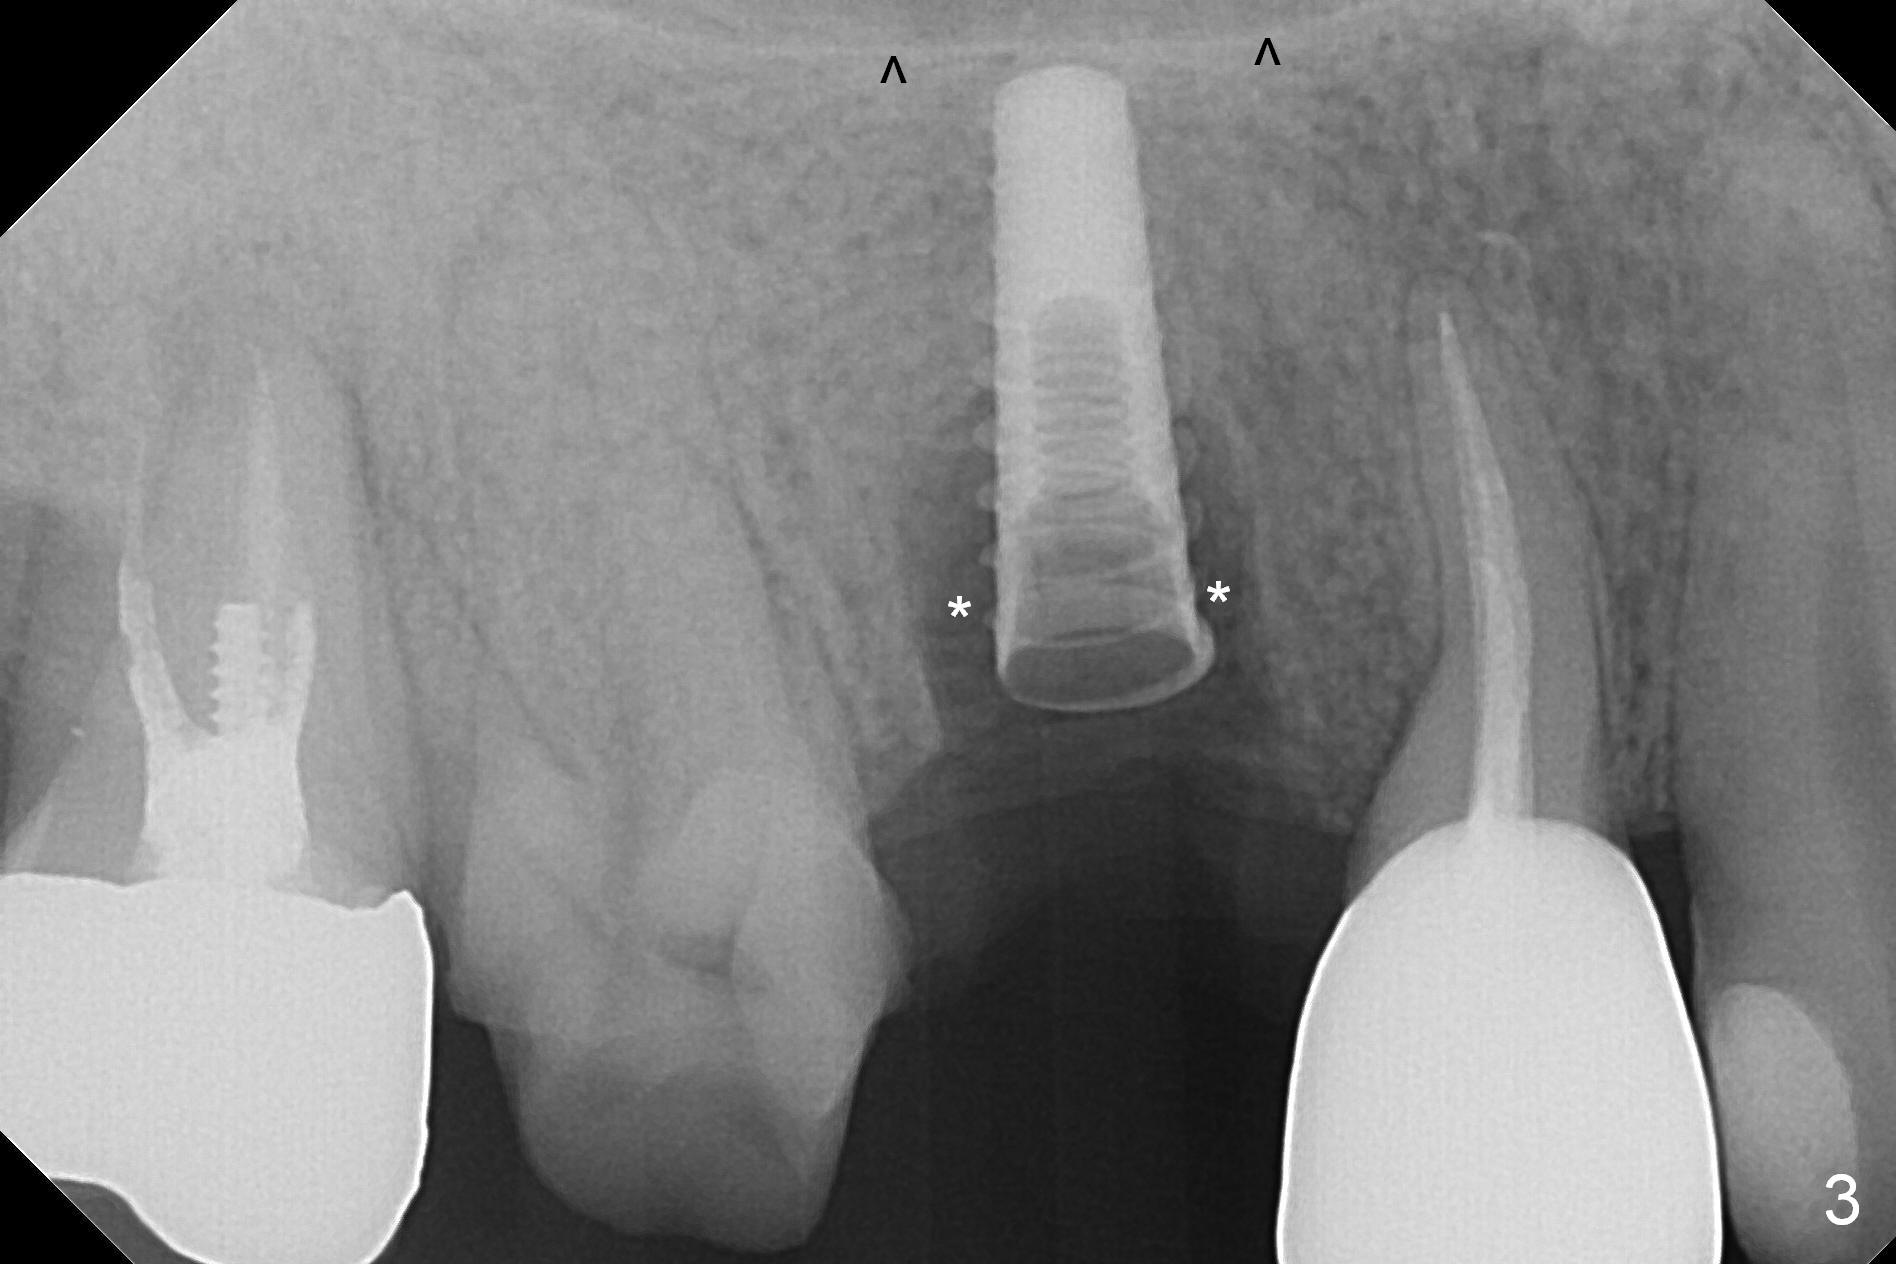

When the tooth #4 with vertical root fracture is extracted, the socket is large, approximately 6x10x10 mm (Fig.1 (mesiodistal x buccopalatal width x depth)). Osteotomy is established in the middle of the socket with 2 mm initial drill for 7 mm, 2.8 and 3.6 mm rounds drills (from DIO Sinus Master Kit) for < 7 mm, and 3.0 and 3.8 mm Magic Expanders. A 4x11 mm dummy implant is placed with insertion torque of 30 Ncm (Fig.2,3 (^: sinus floor)). There is a gap between the socket wall and the implant (*). To reduce the gap and periimplantitis, a 5x11 mm IBS implant is placed with insertion torque > 50 Ncm after further osteotomy using Magic Drills (Fig.4,5). Following placement of 5.5x4(4) mm abutment (A) and bone graft (data not shown), a splinted provisional is fabricated at #3 and 4. The provisional is stable 3 months postop (Fig.6,7). The peri-implant gaps (Fig.4,5) seem to disappear (Fig.6) with the help of bone graft. Bone graft appears to remain between the implant fins (Fig.7 arrows). Impression is taken 4.5 months postop (Fig.8,9). The abutment dislodges 4 months post cementation. After retightening, there is clearance for shim after use of 2 layers of thick articulating paper. Is the abutment screw too short? Or Titanium V is too hard for welding? The abutment/crown dislodges again 1 year 3 month post cementation; it appears that the fact that the implant is placed deep contributes to abutment screw loosening (Fig.10,11). An abutment screw will be buried inside the implant well 10 days post initial retightening.